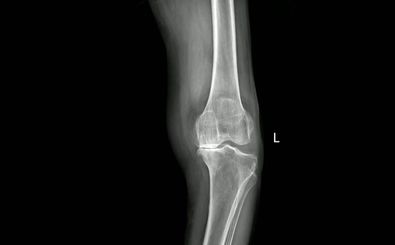

تغییر «شیوۀ راه رفتن» میتواند پیشرفت «بیماری آرتروز» را به تعویق بیاندازد

یک آزمون نشان داده که تغییر زاویه پا میتواند نشانههای آرتروز را کاهش داده و روند تخریب غضروف را کُند کند.